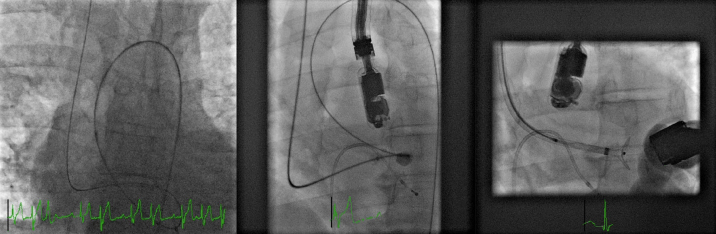

室间隔缺损(VSD)是当今世界上最常见的先天性心脏病之一。虽然大多数是自发关闭,经导管室间隔关闭是一种常见的选择,有症状的患者在成年合适的解剖结构。虽然经食管超声心动图(TEE)和心内超声心动图是该手术最常见的成像方式,但在TEE图像不佳的患者中,经胸超声心动图(TTE)可作为可靠的替代方法。在这里,我们报告了一例肺动脉高压合并肌肉性室间隔缺损的成年患者,由于TEE图像不佳,经皮采用二维TTE缝合。

Ventricular septal defect (VSD) is one of the most common congenital heart diseases worldwide today. Although the majority close spontaneously, transcatheter VSD closure is a common option for symptomatic patients with suitable anatomy in adult age. Although transesophageal echocardiography (TEE) and intracardiac echocardiography are the most common imaging modalities for the procedure, in patients with poor TEE images, Transthoracic echocardiography (TTE) can be used as a reliable alternative. Here we present an adult patient with pulmonary hypertension associated with a muscular VSD which was closed percutaneously using 2-dimensional TTE because of poor TEE images.